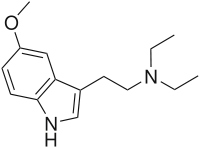

| DET | artificial | H | CH2CH3 | CH2CH3 | N,N-diethyltryptamine | 61-51-8 |